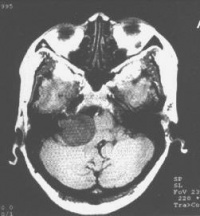

(2)CT及MRI扫描:CT表现为瘤体呈等密度或低密度,少数呈高密度影像。肿瘤多为圆形或不规则形,位于内听道口区,增强效应明显。MRIT1加权像上呈略低或等信号,在T2加权像上呈高信号。第四脑室受压变形,脑干及小脑亦变形移位。注射造影剂后瘤实质部分明显均一强化,囊变区不强化。

(3)CT及MRI检查:目前听神经鞘瘤诊断的标准是Gd-DTDA增强的MRI,特别是当肿瘤很小(<1cm)或在内听道内,CT扫描阴性又高度怀疑肿瘤存在时应该进行GD-DTPA增强的MRI。CT与MRI两种检查有相辅相成的作用,如CT发现有病侧内听道扩大时,增强CT可发现肿瘤对于估计中颅窝入路时颞骨的气化程度及高颈静脉球与后半规管及底的距离有帮助。如果病人已作了CT而肿瘤较大,MRI可提供对脑干压迫的范围Ⅳ脑室是否通畅脑积水、是否存在的情况对可疑听神经鞘瘤或CT检查难于确定时,全序列的MRI可做出鉴别诊断。但也要注意Gd-DTPA的可能假阳性,这与内听道内神经的炎症或蛛网膜炎有关;任何小的接近底部的增强病变应该在六月后作MRI复查,以评估其生长情况。